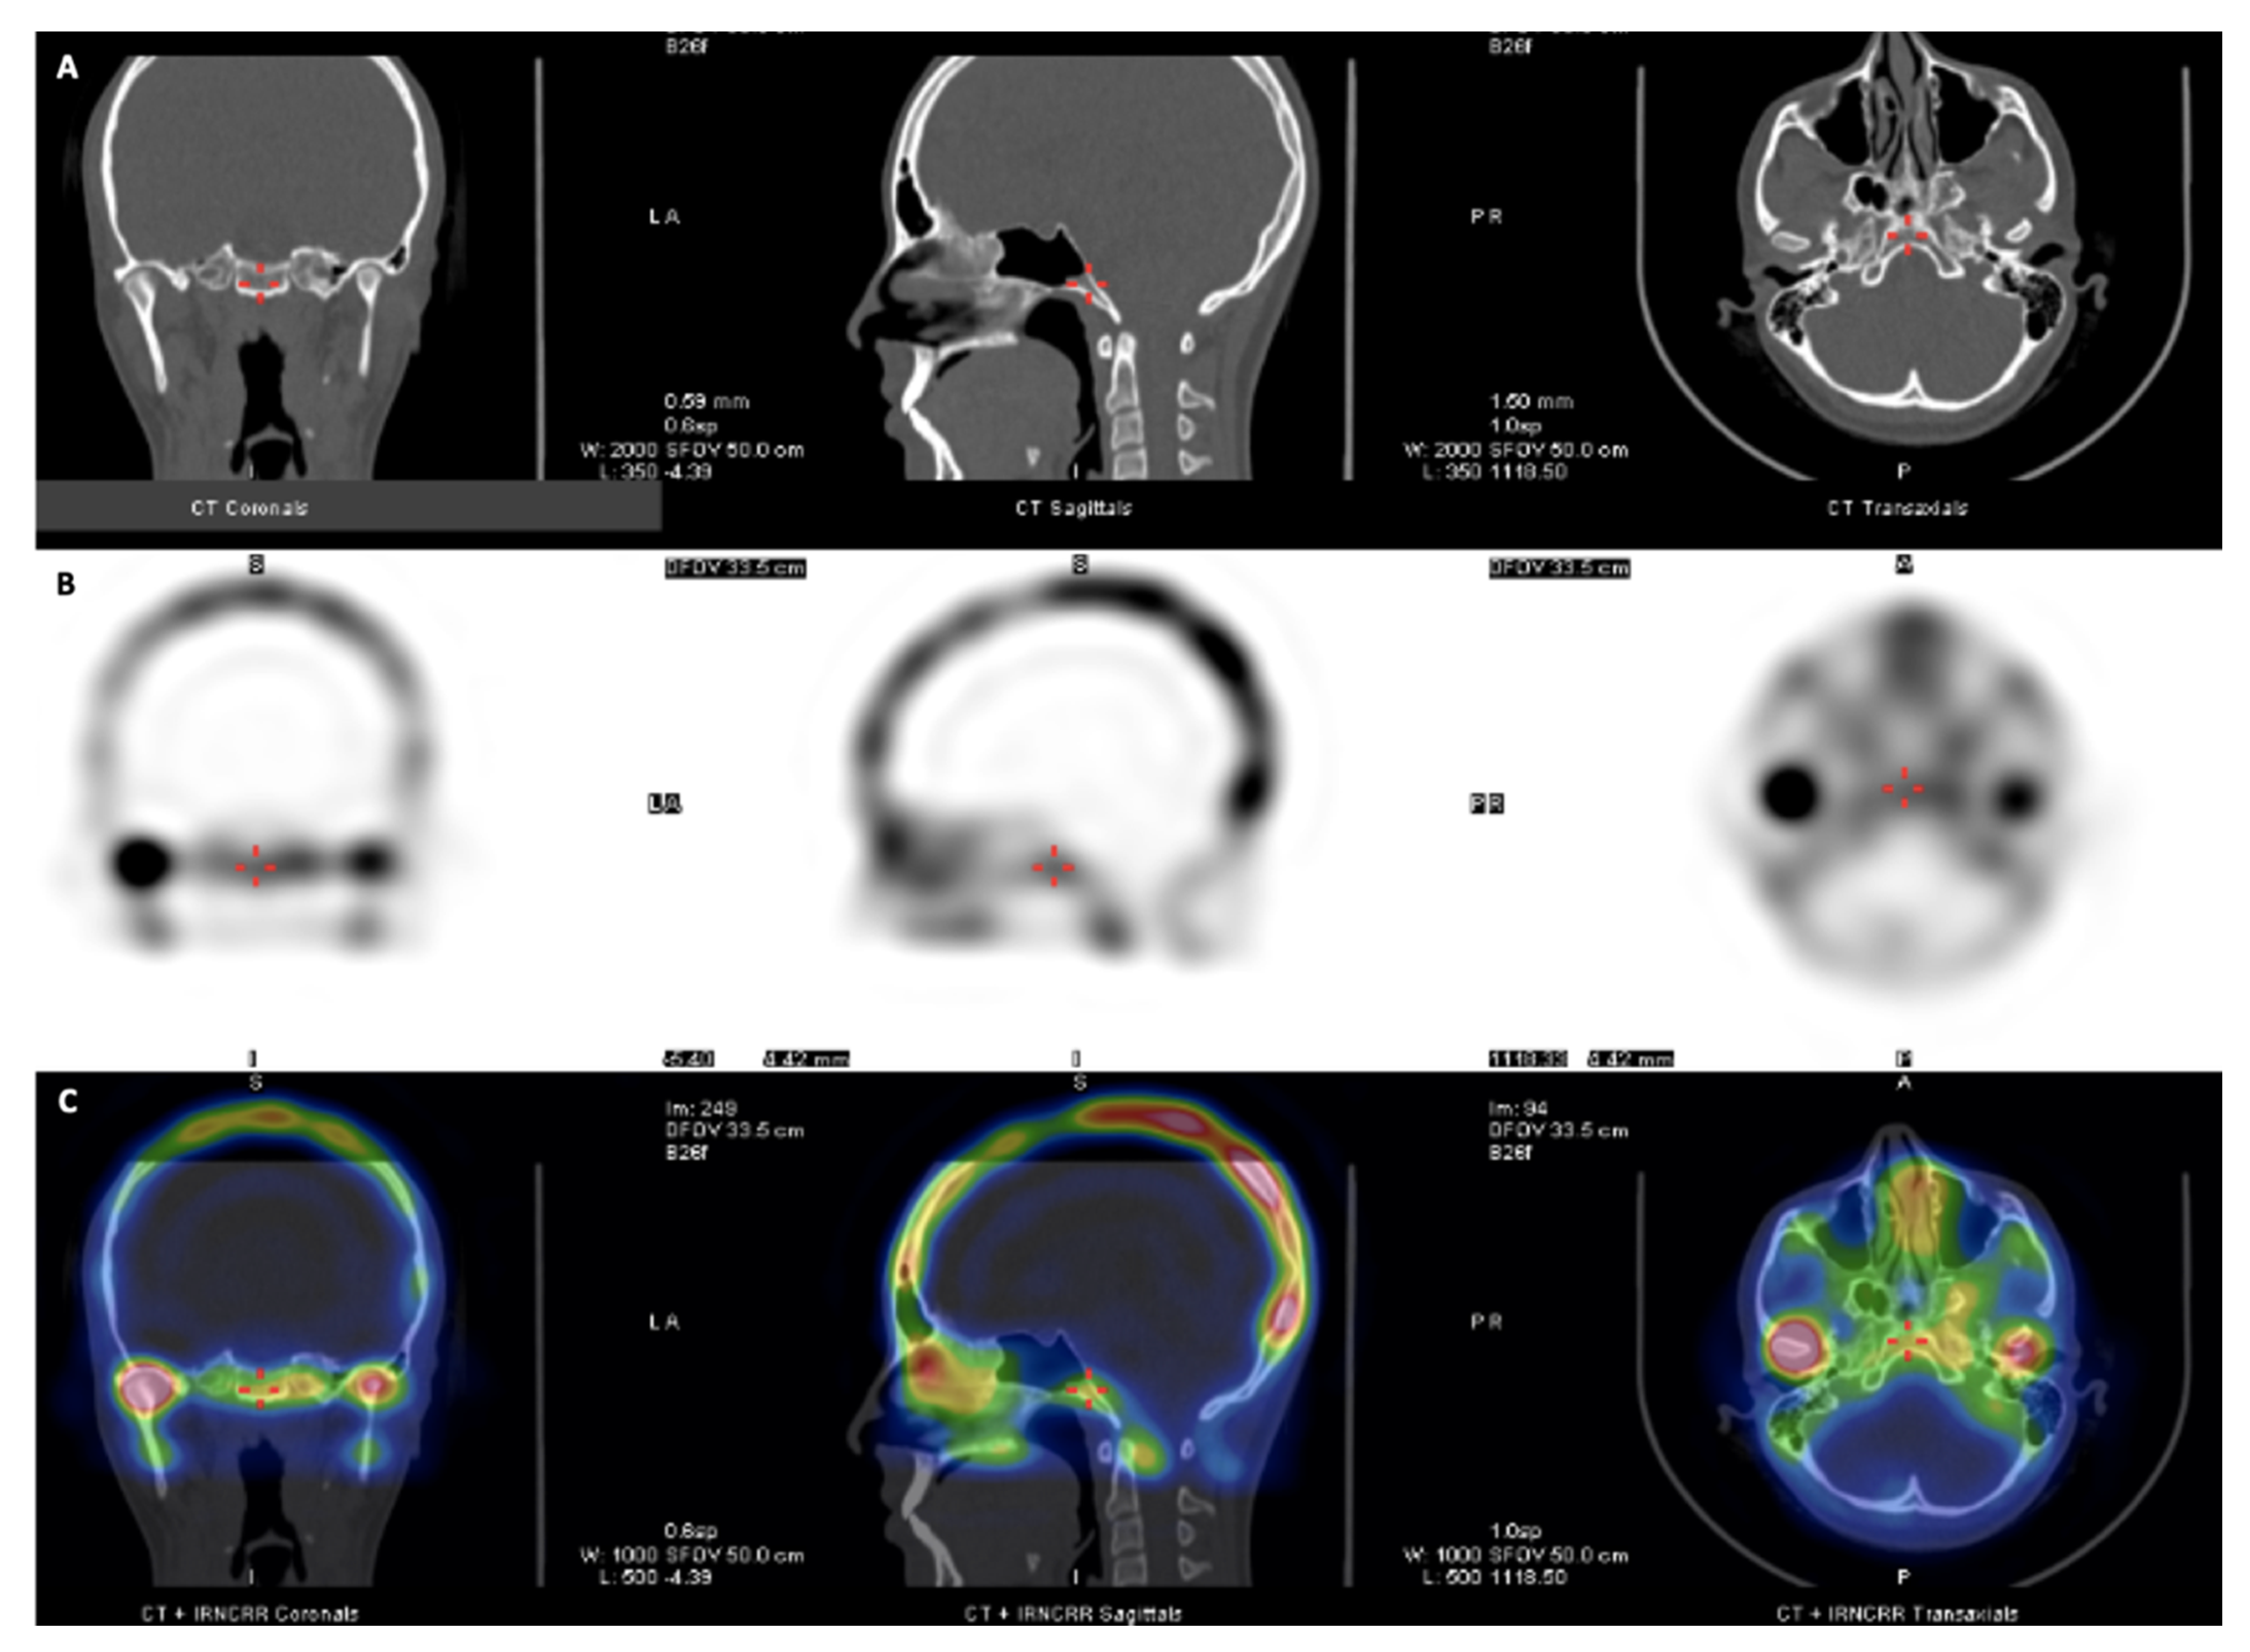

Morphologic Data and Active Hyperplasia